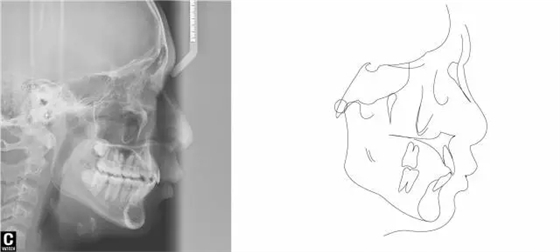

術后全景,側位照。

幾何畫板技術完成術后頭影測量!